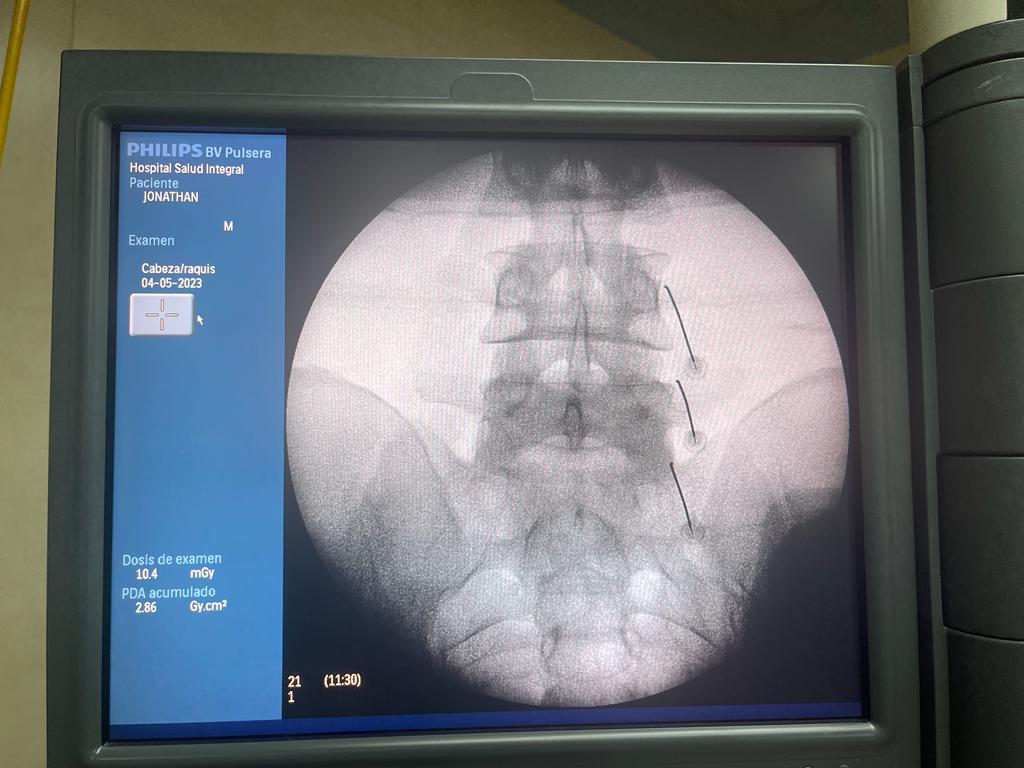

Rizólisis (Ablación por Radiofrecuencia)

Técnica mínimamente invasiva para tratar el dolor crónico articular de la columna

¿Qué es?

La rizólisis es un procedimiento no quirúrgico que utiliza energía de radiofrecuencia para inactivar de forma selectiva los nervios responsables de transmitir dolor desde las articulaciones facetarias de la columna.

¿Para quién está indicada?